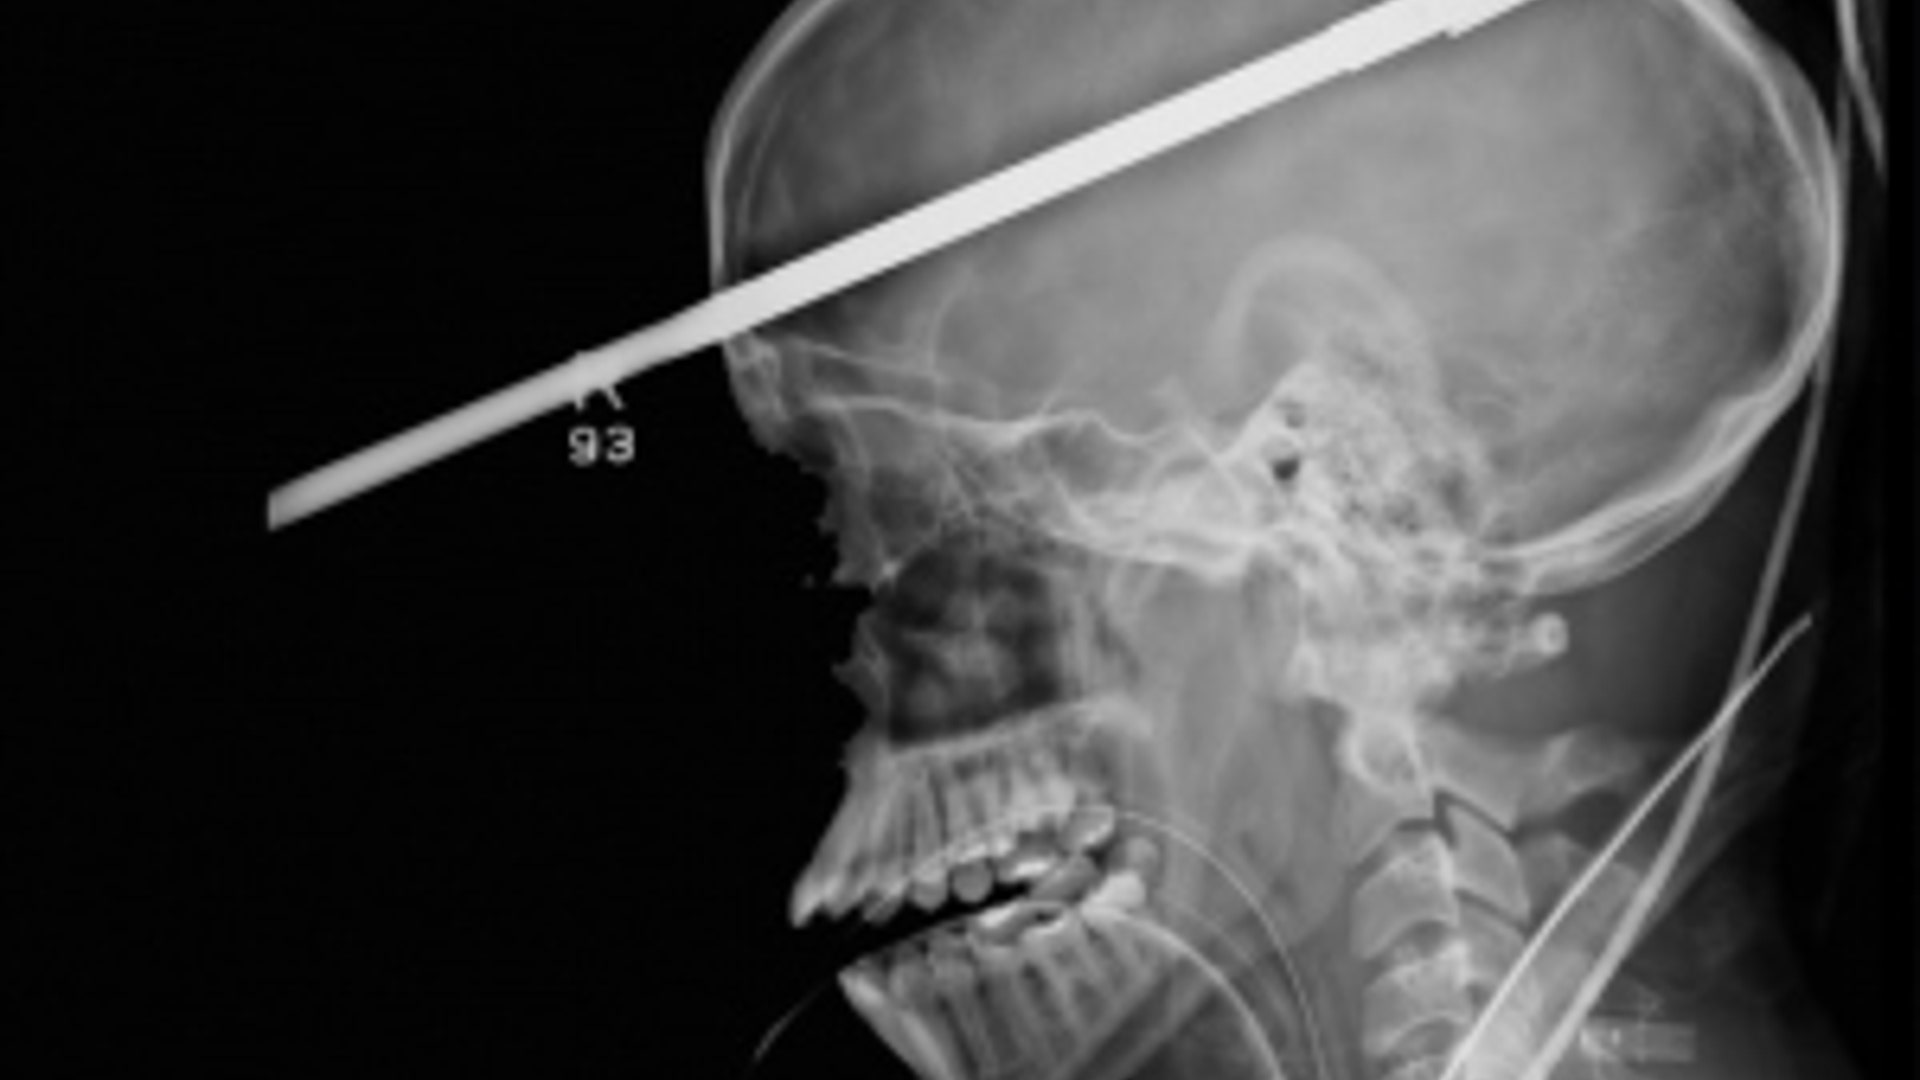

Andrew Linn was in Las Vegas when he fell asleep driving his car last year. He crashed into a chain-link fence and had a pole impale through his head. He was recently reunited with the doctor who saved his life. Dr. Andrew Coates, an associate professor of surgery at University Medical Center, said he was surprised to see Linn was conscious after the accident – and trying to use his cell phone. Linn walked away from the accident with scars, missing teeth and a destroyed palate.read moreFox 5 News - Las VegasShare